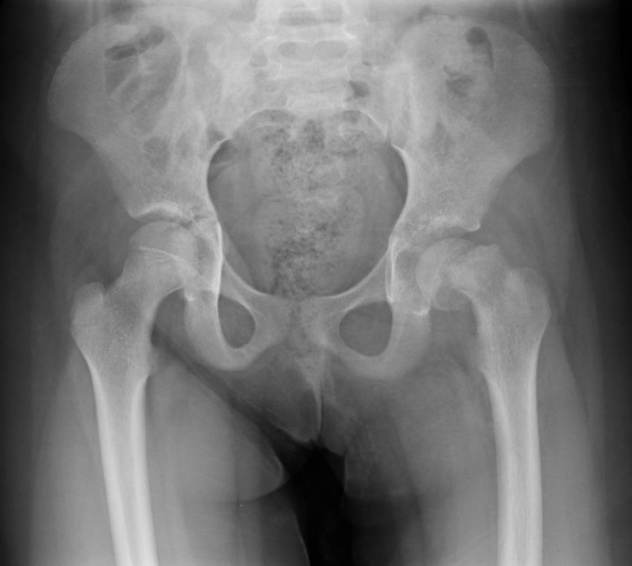

Radiographic findings include asymmetric hips visible on X-ray. Early findings include:

Medial joint space widening (earliest finding)

Small femoral head due to irregularity of the femoral head ossification center

Subchondral fracture.,